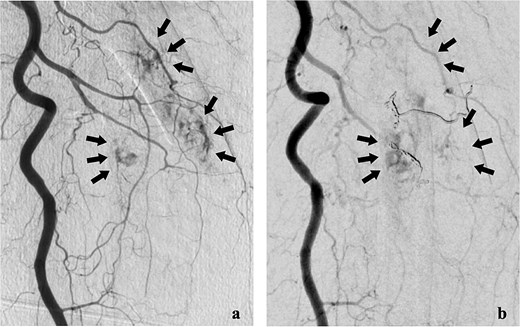

She was transferred to the catheterization laboratory, where coronary and lower extremity angiography revealed 90% stenosis of the left anterior descending artery and tumour blood supply via branches of the deep femoral artery (Figs 2a and 3a).

Coronary angiography findings. (a) Pre-treatment angiography showing 90% stenosis of the left anterior descending artery. (b) Post-treatment angiography showing improved blood flow in the left anterior descending artery after percutaneous coronary intervention.

Dual antiplatelet therapy (DAPT) with aspirin and prasugrel was initiated, followed by PCI with drug-eluting stents (DES) from the left main coronary trunk into the anterior descending artery (Fig. 3b).